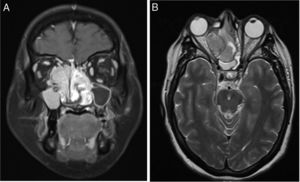

Mujer de 37 años con episodios de epistaxis y sensación de cuerpo extraño en fosa nasal. La resonancia magnética mostró extensa lesión neoformativa de 6cm con áreas necróticas comprometiendo la totalidad de la cavidad nasal, y extensión hacia la fosa craneal anterior, destrucción de la lámina papirácea con marcado efecto de masa hacia la cavidad orbitaria ipsilateral (fig. 1). La biopsia fue reportada como carcinoma neuroendocrino de células pequeñas (CNCP) (fig. 2). El CNCP es una enfermedad rara en la región nasosinusal, la sintomatología es inespecífica e incluye insuficiencia respiratoria, rinorrea y epistaxis. El comportamiento de esta neoplasia es localmente agresivo. Existe poca experiencia en el manejo de este tipo de tumores, la resección amplia como tratamiento inicial está indicada, y la radioterapia y/o quimioterapia como adyuvancia.